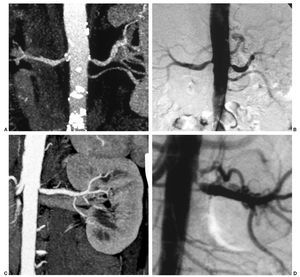

Las estenosis de grado II se consideraron hemodinámicamente significativas1 (fig. 1). La presencia de dilatación arterial posestenótica, la disminución del tamaño renal, el adelgazamiento de la cortical renal y el nefrograma retrasado y persistente fueron interpretados también como signos indirectos relacionados con la presencia de patología vascular2,9.

Fig. 1. (A) Reconstrucción de tipo máxima intensidad de señal (MIP) coronal en la que se muestran sendas estenosis de grado II en los ostia de las arterias renales principales. Hay calcificaciones profusas, pero que no impiden la correcta evaluación, y una dilatación posestenótica en la arteria derecha. En el lado izquierdo se identifica también un vaso accesorio de características normales. (B) Angiografía con sustracción digital (ASD) en la que se corroboran los hallazgos de la tomografía computarizada multicorte con estenosis en los vasos arteriales. (C) Estenosis de grado III en el ostium de la arteria renal izquierda; MIP coronal. (D) Detalle de la estenosis arterial de alto grado, preoclusiva, en la ASD.